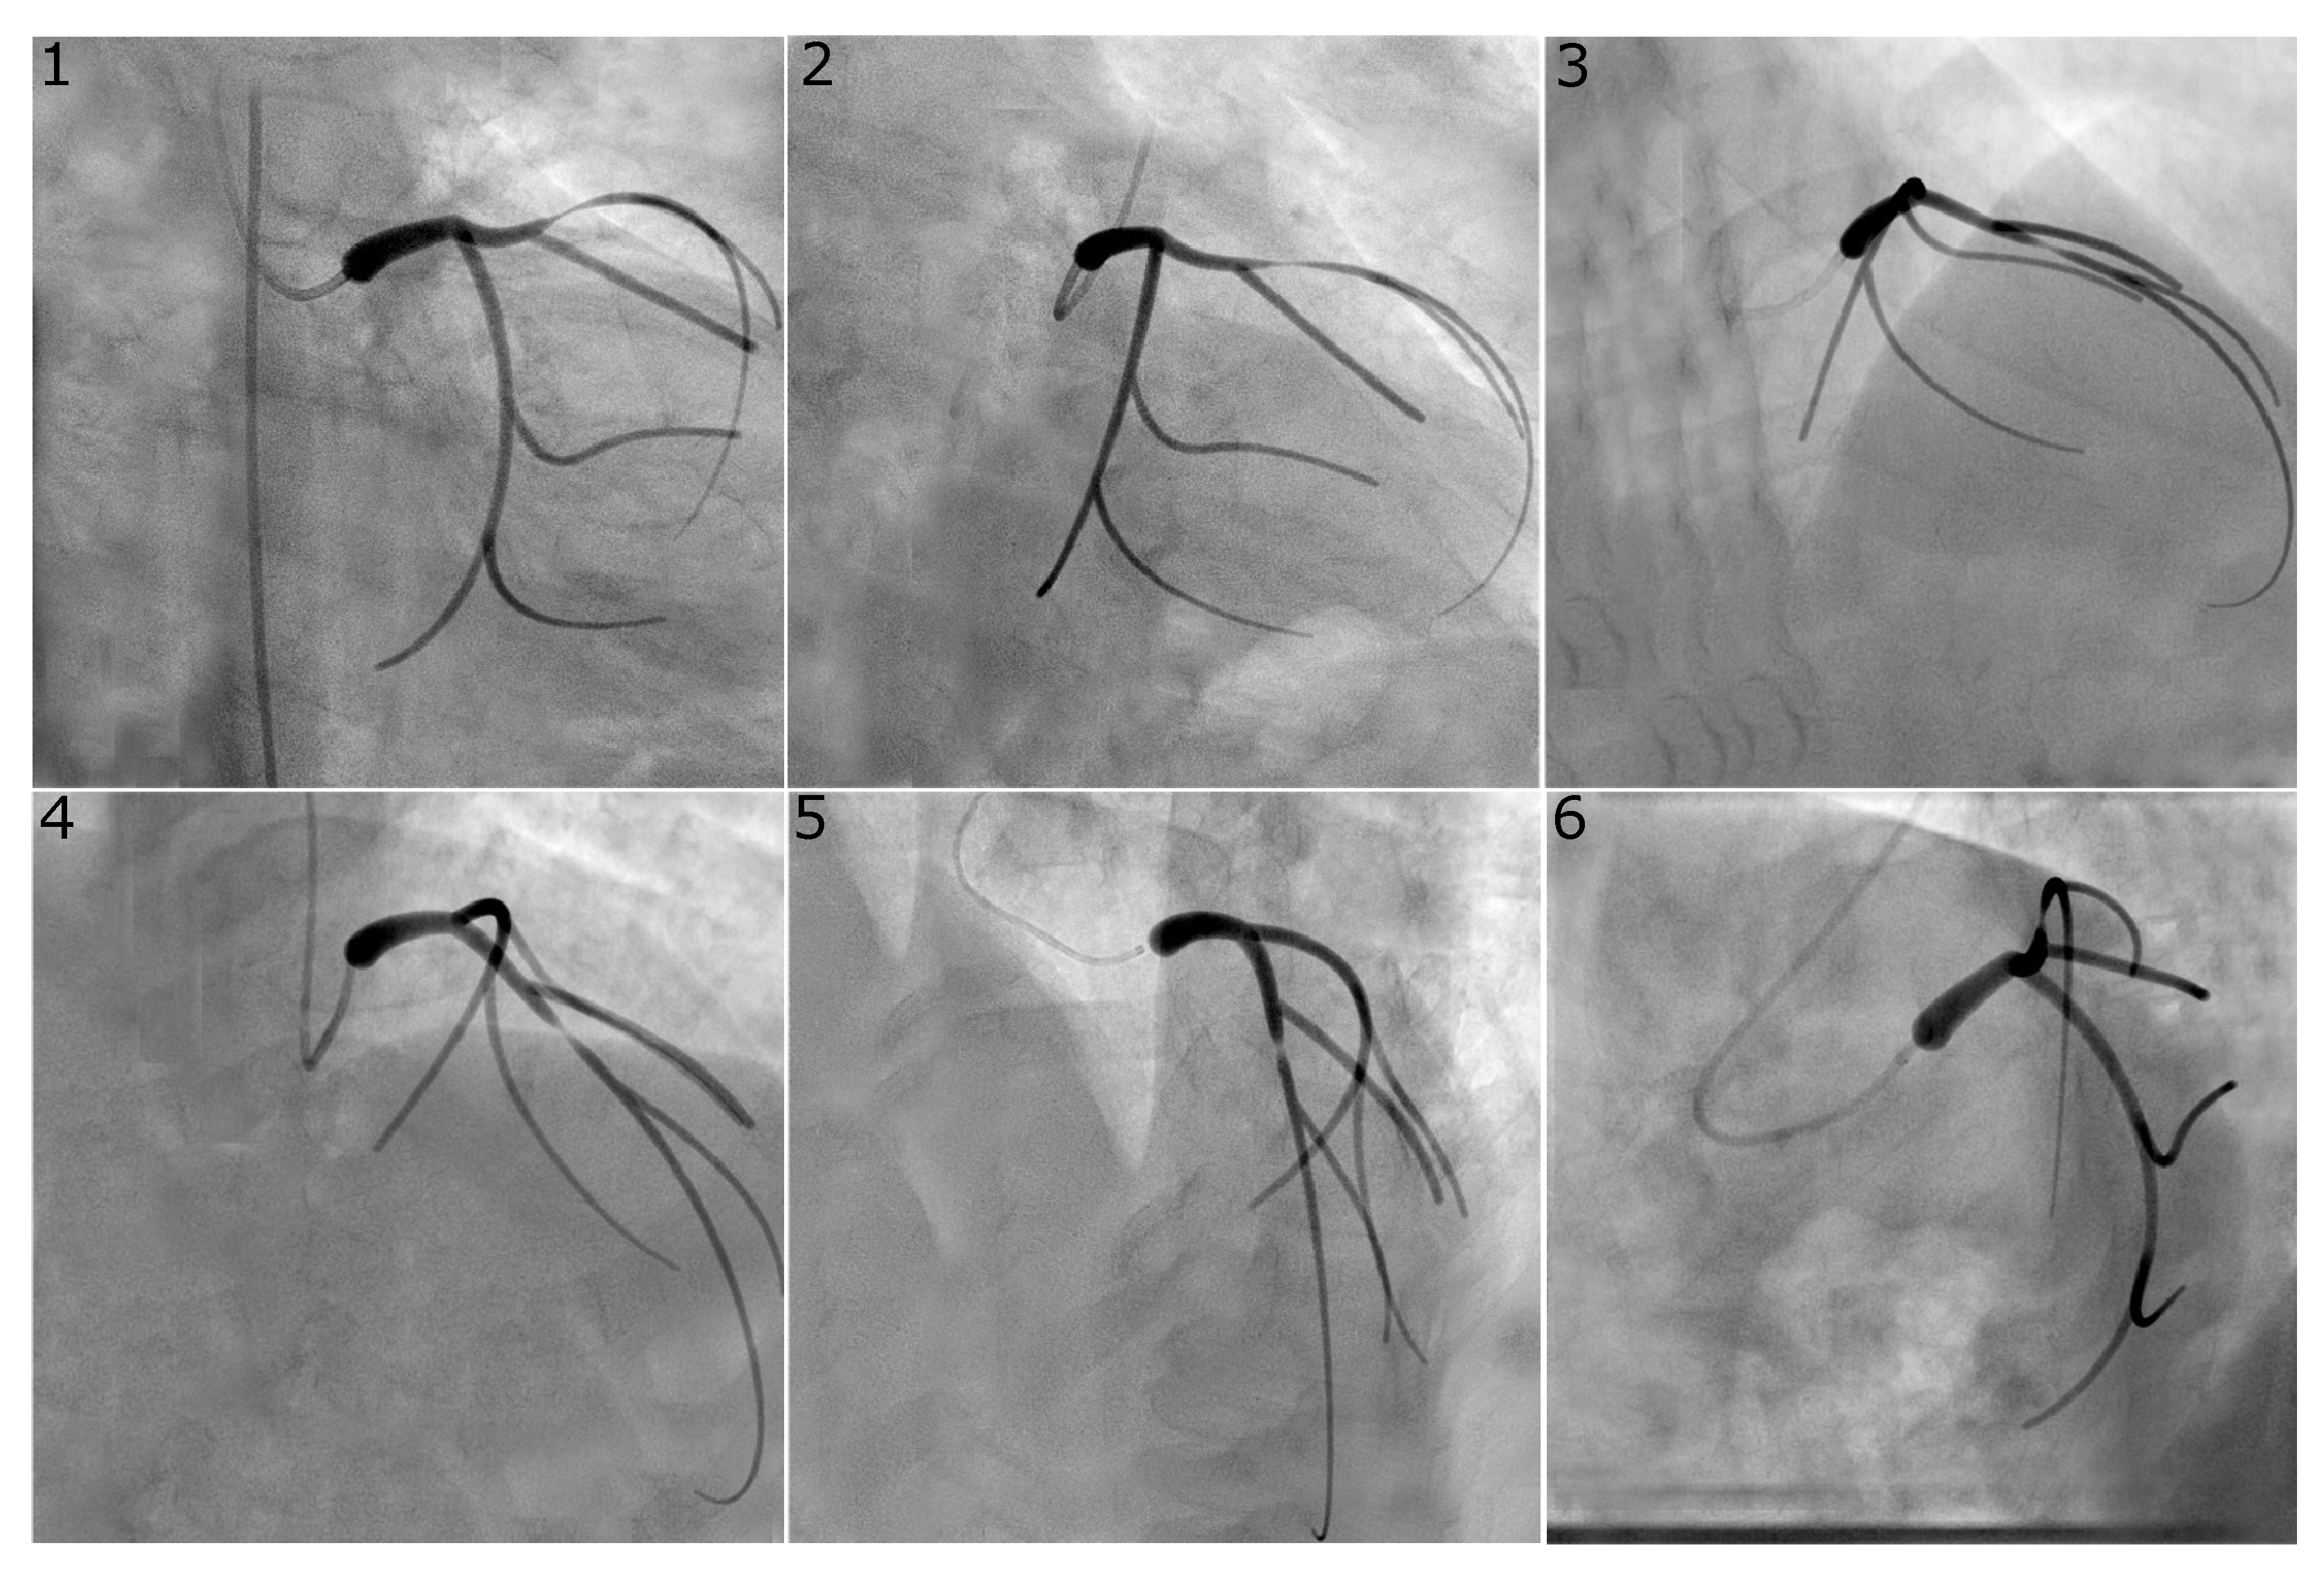

For each stenosis location and degree, the phantom was projected onto three pairs of viewing angles which correspond to those typically used in the catheterisation laboratory to visualise stenoses in these locations. With reference to Table 1, the image pairs used to reconstruct the LCX were obtained using views 1 and 2, 1 and 6, and 2 and 6, while for the LAD, views 3 and 4, 3 and 5, and 4 and 5 were used. This resulted in 120 unique 2D images and 120 image pairs used for segmentation and 3D vessel reconstruction. Representative “virtual angiograms” are shown in Figure 2 and Figure 3.

Figure 2.

Virtual angiogram for all views of the left coronary system with a concentric stenosis of diameter reduction in the LCX. Views , and were used to reconstruct this vessel as they are usually selected in the catheterisation laboratory since they avoid vessel overlap and excessive foreshortening for the vessel of interest.

Figure 3.

Virtual angiogram for all views of the left coronary system with an eccentric stenosis of type “8040” in the LAD. Views , and were used to reconstruct this vessel as they are usually selected in the catheterisation laboratory since they avoid vessel overlap and excessive foreshortening for the vessel of interest.

Figure 2 and Figure 3 show representative examples of virtual angiograms generated for the two coronary arteries considered in this study. Figure 2 shows the case in which a concentric stenosis, of diameter reduction, affects the LCX. This case is included here for theoretical interest as it allows for an appreciation of the severity of a stenosis of this diameter reduction, but it is of smaller concern to the clinical community, due to the certainty of its severity. Figure 3 shows the case in which the LAD is affected by stenosis, this time of the eccentric type, with diameter reductions of and in the two orthogonal directions. This case shows how eccentric stenoses can appear differently in different views, and showcases that the choice of the view pair can result in either underestimation or overestimation of the severity of the stenosis (thus, overestimating or underestimating the radius, respectively).